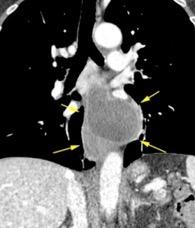

3 rasgos: Conexión entre mediastino y lesión pancreática. Derrame pleural Hallazgos de pancreatitis. Matsusue E et al.Three cases of mediastinal pancreatic pseudocysts. Acta Radiol Open. 2016 .